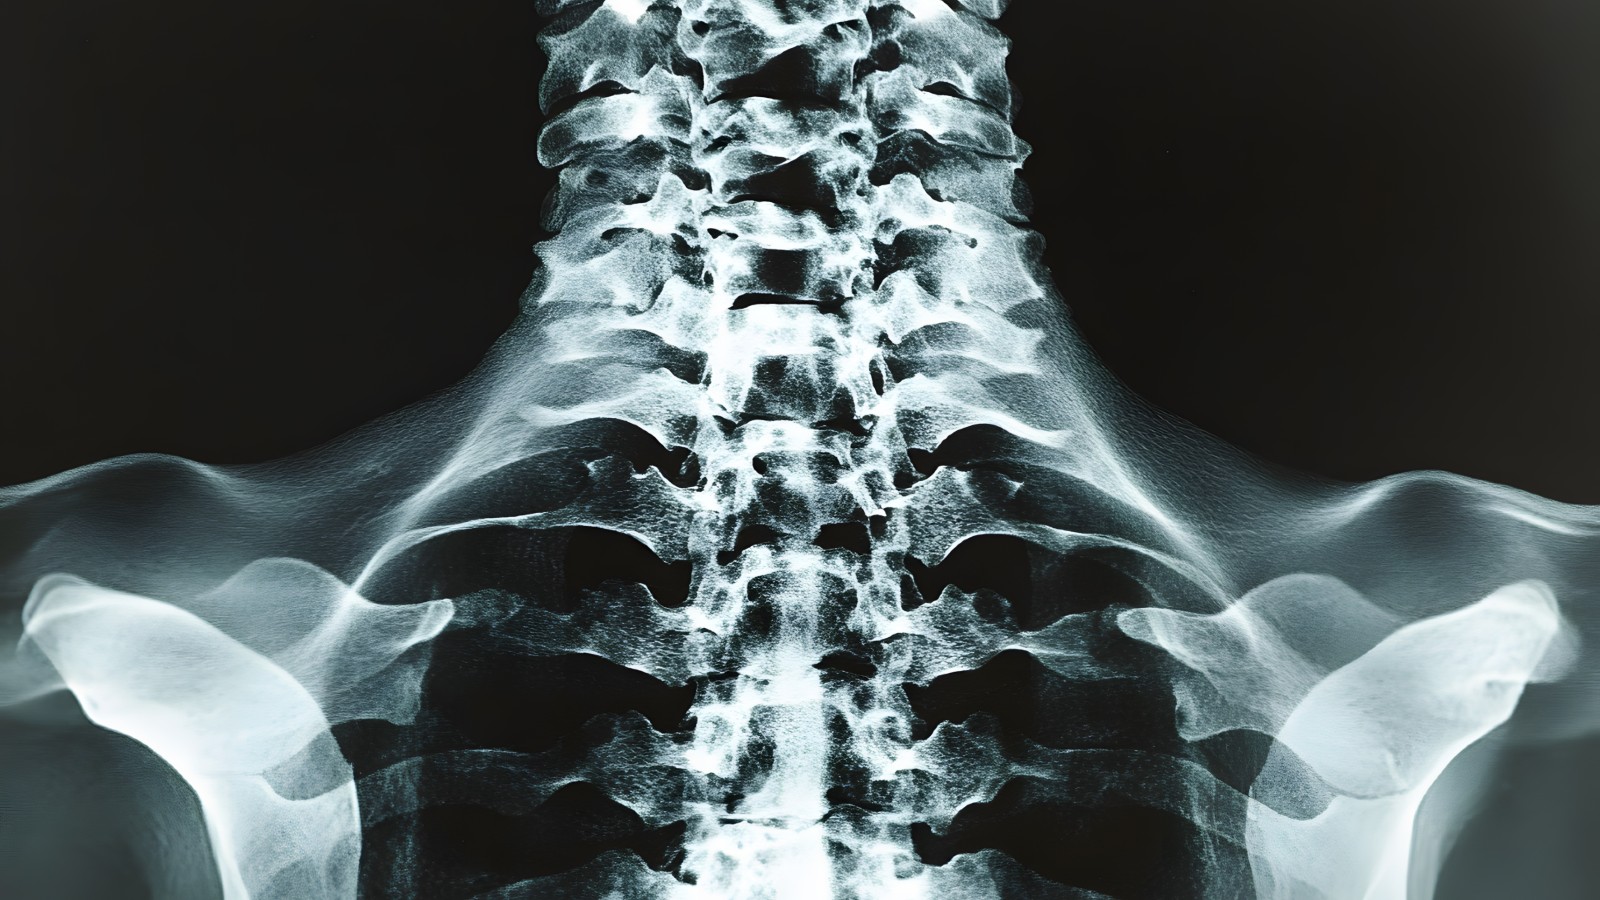

Cervical stenosis is the narrowing of the spinal canal in the neck. Once the narrowing becomes severe enough to injure the spinal cord itself, it leads to a condition called cervical myelopathy. While mild narrowing may cause few or no symptoms at first, this long-term squeezing can interfere with the spinal cord’s ability to transmit signals between the brain and body, often leading to weakness, balance problems, and hand clumsiness that can worsen over time.

How does this narrowing happen? Your spinal canal is a protective tunnel that runs through your neck bones (the cervical vertebrae) and houses your spinal cord. Cervical stenosis means the tunnel has narrowed, often due to natural aging, arthritis, bone spurs (growths), herniated discs, or thickened ligaments.

Imaging Studies

Magnetic resonance imaging (MRI) is the gold standard for diagnosing cervical myelopathy. MRI shows the area of compression and any signal changes inside the spinal cord, indicating tissue damage. CT scans and X-rays can also be used to assess bone spurs or alignment issues, as well as instability that can contribute to stenosis.